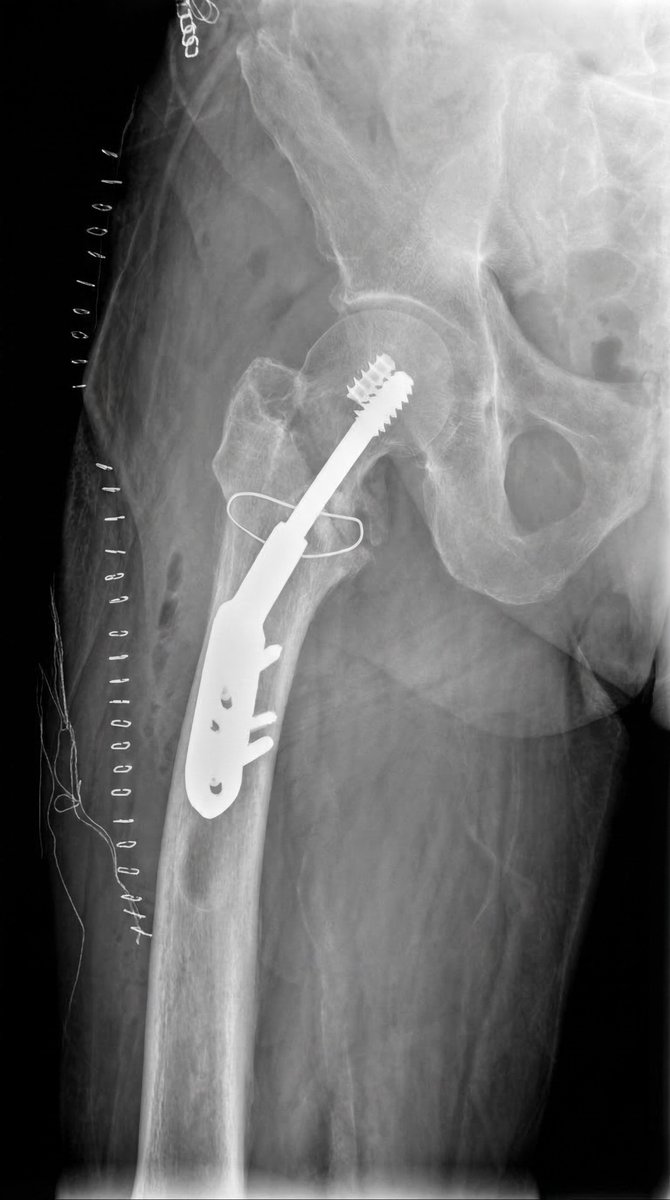

@traumaticum @ImprezowyKotek @orthobullets @orthotraumamd I see why a DHS… has the compression option that not all nails have, and it’s easier to add antirrotation or extra fixation screw in case needed. Also may let you correct valgus using the implant instead of forcing you to have it reduced before nail insertion. I like it.